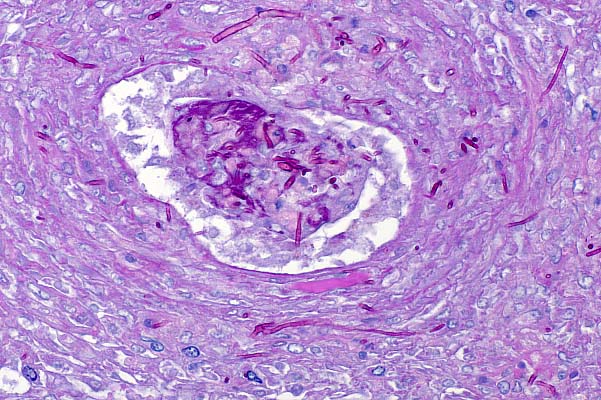

- Sections of skin containing an expansile, nonencapsulated,

multilobular, pigmented dermal mass which extends to both lateral

and ventral borders in some sections. The mass is composed of

whorls, interlacing bundles, nests and fascicles of a uniform

population of spindle cells on a fine fibrovascular stroma. The

cells are spindle to stellate with indistinct cell borders, moderate

amounts of eosinophilic fibrillar cytoplasm with varying amounts

of coarse to fine golden brown/olive green pigment granules.

The nuclei are ovoid to polyhedral with coarsely clumped chromatin

and a single, variably distinct, round, magenta nucleolus. The

mitotic index is less than l/HPF. Pigment granules are birefringent

on polarized light.

- Case 29-1. Dermis. Variably pigmented spindle shaped

cells contain anisotropic crystalline material when viewed under

polarized light.